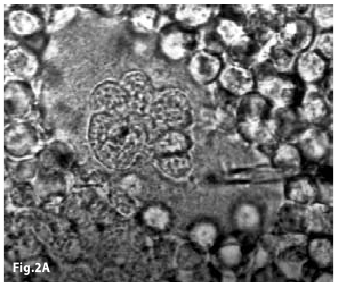

Figure2A